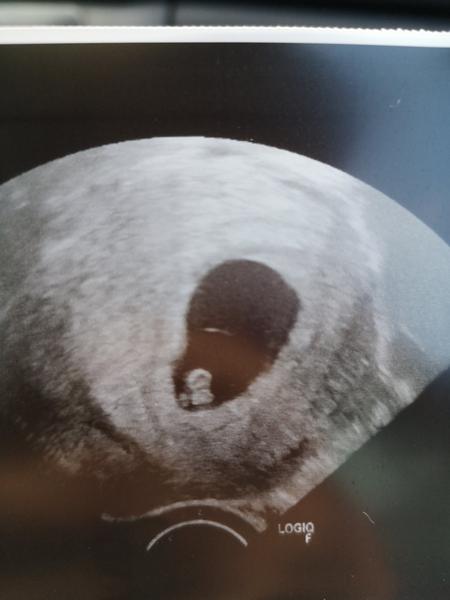

@mirpet @adkaaa @bobulkapetka @julinka2787 @peggie Ahojte dievcence. Tak dnesne sono dopadlo na jednicku. Babika ma 0,63cm a 💓 bilo neskutocne krasne. Termin nam stanovili na 16.5.2019. Takze extra pre teba @peggie nevzdavaj sa!!! Oplati sa pockat na vsetky vysetrenia a az tak ist na vklad.

@lyzinka super teším sa 😍😍 inak vyzerá na foto ako malinky ⛄️🙂